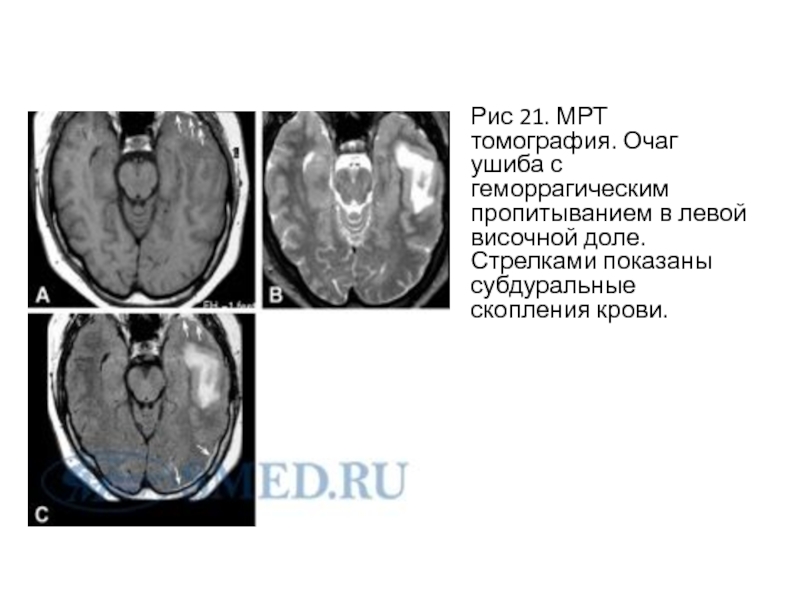

Слайд 16Рис 21. МРТ томография. Очаг ушиба с геморрагическим пропитыванием в

левой височной доле. Стрелками показаны субдуральные скопления крови.